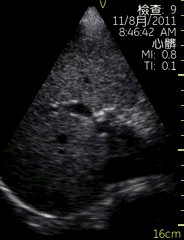

Vscan临床图片 腹部